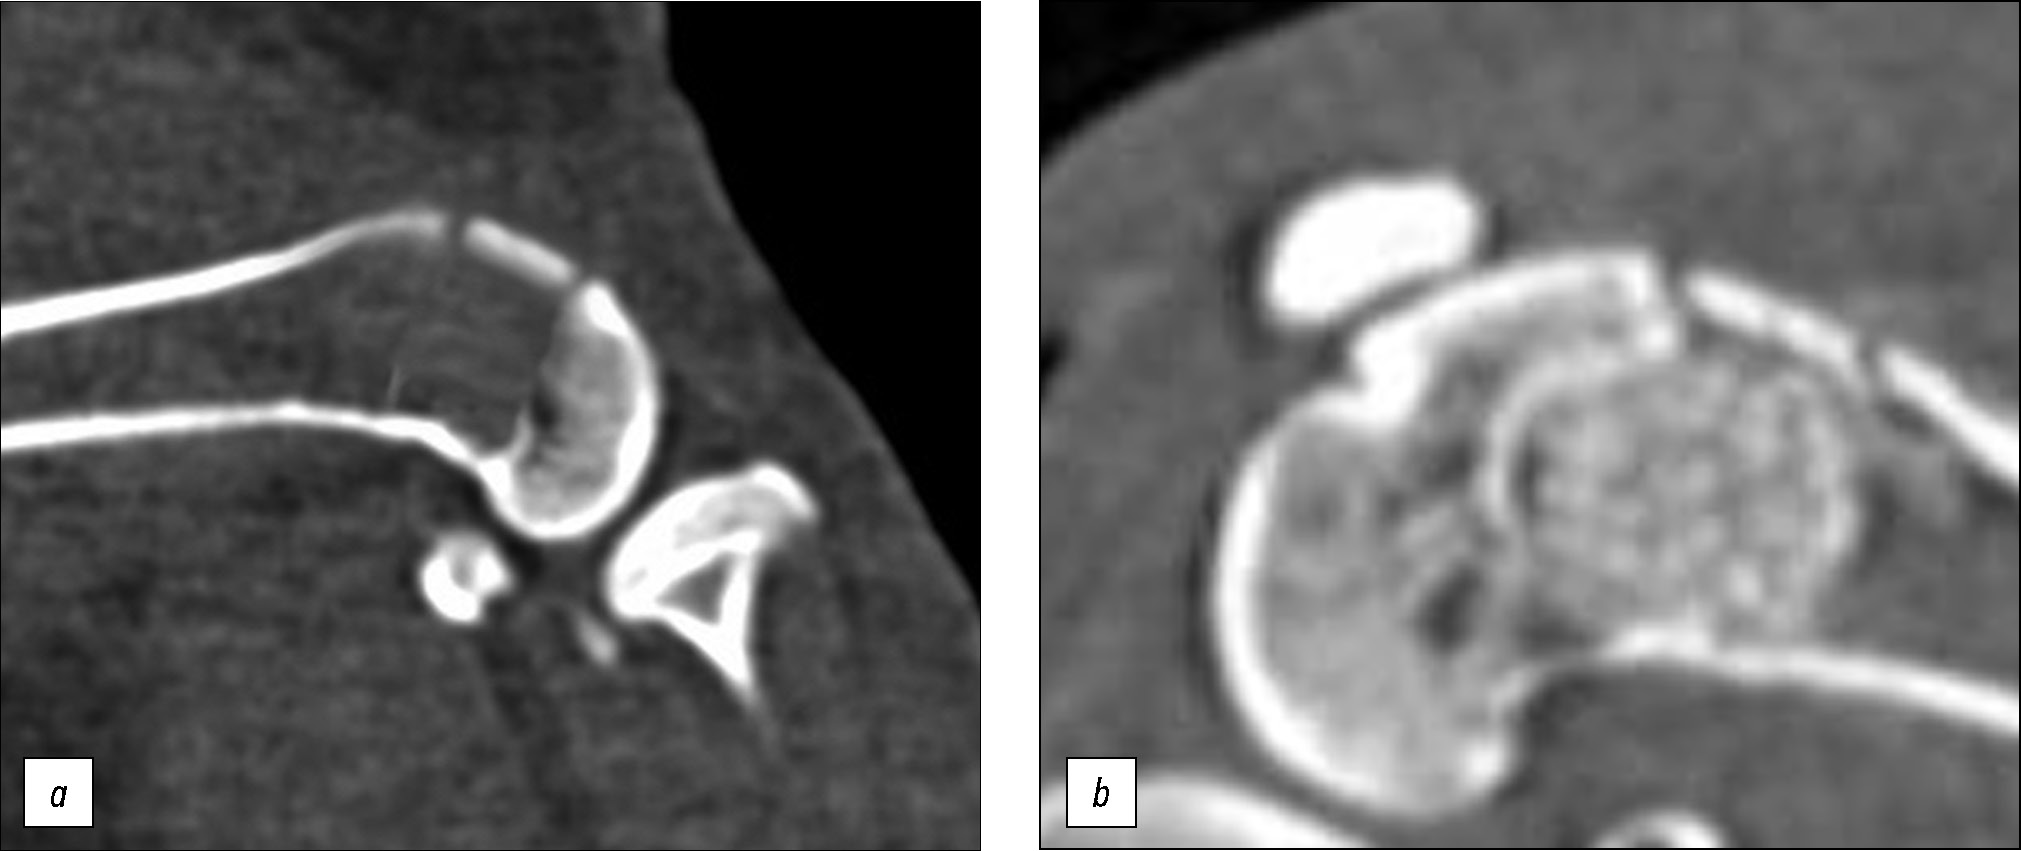

Fig. 1. CT of the metaphyseal defect area: a — the zone of compression defect of the distal metaphysis of the femur of a laboratory animal, group 1 (CT-scan), b — the zone of compression defect of the distal metaphysis of the femur of a laboratory animal, group 3 (CT-scan).

All animals underwent a standardized compression defect of the metaepiphyseal part of the femur under intramuscular sedation with a solution of tiletamine hydrochloride and zolazepam hydrochloride (with the dosage calculated based on body weight), which was filled with the test material in the experimental groups, whereas in the control group, plastic replacement of the defect was not performed. Surgery involved the formation of a full-layer fragment of the cortical plate measuring 10 × 5 mm along the anterior–outer surface of the distal metaepiphysis using a milling saw, followed by its impression to a depth of 8 mm. Moreover, the volume of the formed defect cavity was identical in all series of the experiment and amounted to 400±20 mm3 (RU patent no. 20802431, dated August 28, 2023). After elevation of the osteotomized fragment, the formed post-compression bone cavity remained intact (Fig. 1a), or 0.4 cm3 of synthetic material was placed in the defect site (Fig. 1b). The cortical plate was fixed in the maternal bed, and the soft tissues were sutured layer by layer.